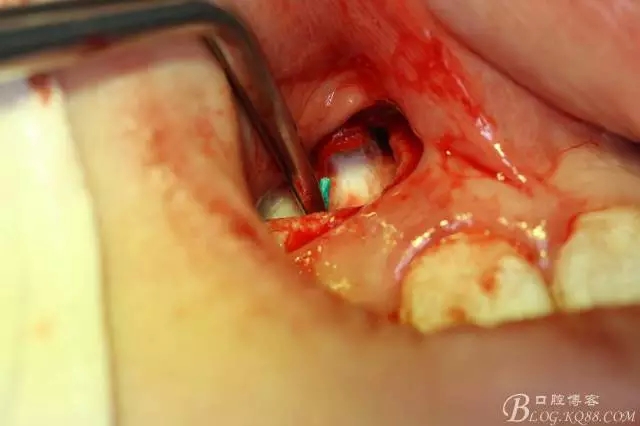

病例資料: 患者、柴xx、女、16歲。專科檢查及病歷如下圖: 患者同意我院正畸科建議,遂轉(zhuǎn)診倒外科。術(shù)前簽知情同意書。 治療過程: 圖1.術(shù)前的CBCT檢查:13阻生,疑為含牙囊腫。縱剖面顯示12牙根吸收至根尖1/3。 圖2.局部麻醉下 。行唇側(cè)弧形切口,12松動不到1°。 圖3.翻瓣、暴露骨面。 圖4.去骨、 暴露13牙冠 圖5.去骨、逐漸顯露13。 圖7.拔除13. 圖8.摘除囊壁 圖9.必須完整剝離囊壁。 圖10.摘除囊壁后形成的骨腔 圖11.超聲骨刀12根尖倒預(yù)備 圖13. 消毒棉球骨腔內(nèi)隔濕血液,紙尖干燥倒預(yù)備好的根管 圖14. 紙尖無血即可 圖15。MTA倒充填 圖16.骨腔填塞膠原蛋白海綿 圖17.拔除的13及摘除的囊壁 圖18.縫合 圖19.術(shù)后x線根尖片影像:MTA封閉根尖